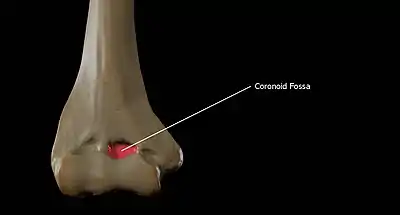

Above the front part of the trochlea is a small depression, the coronoid fossa, which receives the coronoid process of the ulna during flexion of the forearm.

The coronoid fossa is the medial hollow part on the anterior surface of the distal humerus. The coronoid fossa is smaller than the olecranon fossa and receives the coronoid process of the ulna during maximum flexion of the elbow.

Coronoid Fossa of the Humerus